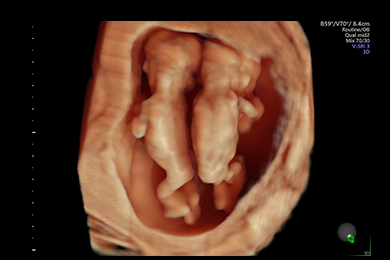

Gemini 13. SSW, Rückenansicht, 3D